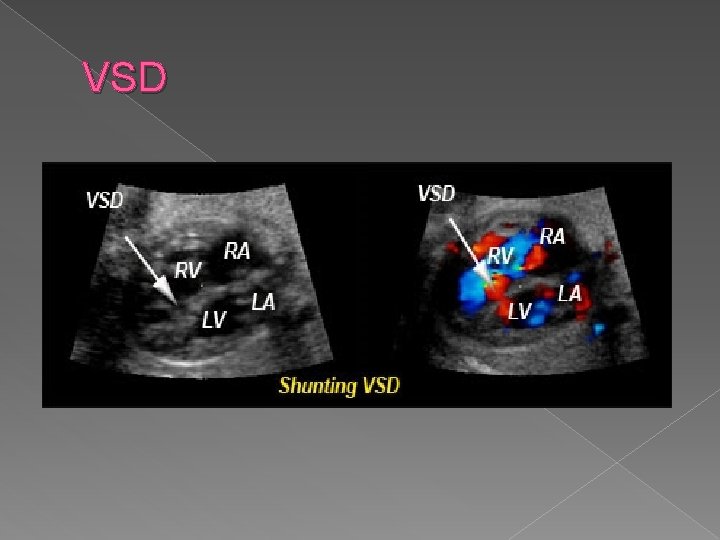

Ventricular Septal Defect (VSD) � Ranks first in frequency of all cardiac anomalies. Caused by incomplete closure of interventricular IIV) foramen and failure of the membranous part of IV septum. VSDs are the most teratogen-associated fetal defect, and are associated with other cardiac anomalies 50% of the time.

Sonographic findings: � Demonstration of an opening between the ventricles on 4 chamber view � Bidirectional flow demonstrated with color Doppler � Larger defects are easier to diagnosis.

�A ventricular septal defect (VSD) is a defect in the ventricular septum, the wall dividing the left and right ventricles of the heart. � Congenital VSDs are collectively the most common congenital heart defects.

Ventricular septal defect (VSD) › Ranks first in frequency of all cardiac anomalies › Opening between the two ventricles › Commonly caused by a teratogen-associated fetal defect. › Associated with other cardiac anomalies 50% of the time. › Seen by demonstrating an opening between the ventricles on a 4 chamber view

VSD

VSD